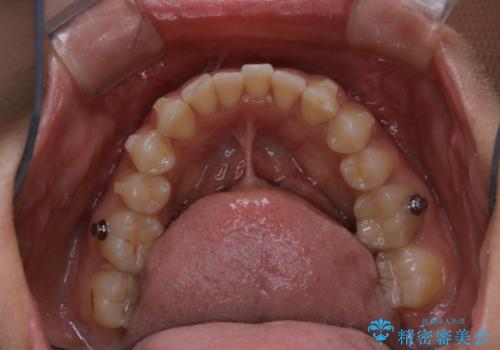

- インビザラインでの矯正治療中に、着色や汚れが気になるとのことでした。PMTC60分コースを行いました。

インビザライン治療中には、歯の表面にアタッチメント(効率的に歯の移動をするもの)を設定します。そのため歯ブラシでは届きにくい細かい部分などに、歯石や着色がついてしまうことがあります。着色などを放置していると、着色なのか、虫歯なのかの判別もしずらく正確にお口の中の状態を診断できません。

矯正治療中も定期的に歯科医院にてPMTCを受けて、お口のケアを行うことをおすすめします。